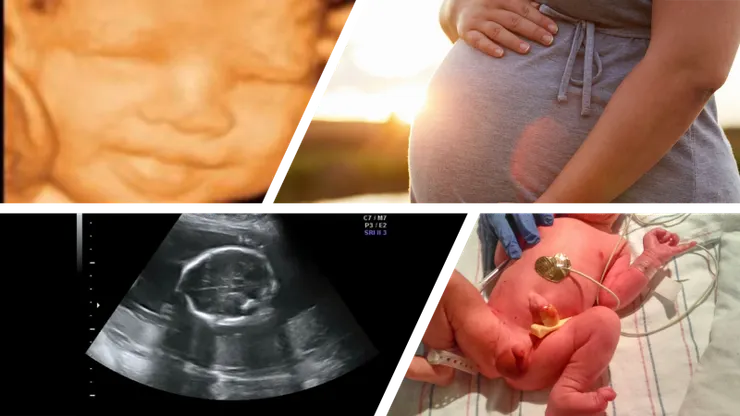

最後來講講我的經歷吧,我們在嘗試懷孕這個部分沒有遇到什麼困難,我老婆算好日子那一個經期就懷孕了,如果有相關問題一定要儘早尋求醫療幫助;我一個朋友一直有相關的問題,在婦產科的幫忙下,兩個月後就懷孕了。第一週期過得很順利,老婆除了變胖一點也沒什麼懷孕的徵狀,第二周期開始老婆開始出現晨吐,血糖過高的問題,開始減低碳水化合物攝取,過了兩個月婦產科醫生覺得小孩子有偏小的問題,便建議我們去看營養師,在營養師的幫忙之下,大部分的東西都回到正常軌道,因為小孩過小的問題,我們在醫師建議下總共做了七次超音波跟都普勒,不過因為是醫師建議,所以保險全額;時間來到36週5天,有點出血的狀況,我們就到醫院準備,不幸的事會診之後被告知可能是胎盤剝離,幸運的是黎族月的37週剩三天,醫師建議直接住院到37週看要手動破水還是剖腹直接生產(37週前醫生擔心小孩子的呼吸系統尚未健全,住院24小時監控小孩心跳指數,一有緊急情況直接開刀)。三天後醫生建議直接破水,我們選擇無痛麻醉,我老婆本來想試試看不使用無痛但是一小時後他就受不了了。出生之後奶水很少搭配配方奶度過,小孩體溫較低,醫生事告知說早產嬰兒比較會有體溫控制的問題,我跟我老婆輪流把他抱在懷裡幫他控制溫度。回家後,第一次去看兒醫還是被告知體溫稍低,直接轉診醫院怕有感染,後來又在醫院三天,他體溫系統就正常了。因為那一年保險選了蠻高階的保險,我們整個生產加上產後一週的醫療費用大概為兩萬五千多,但是我們只實付$30第一次婦產科co-pay,第一次去兒科的錢,體溫異常住院的錢,全部加起來大約是$500左右,我們是產後三天聯絡保險公司將小孩子加入保險,產後十天才正式生效,但是小孩子那次異常溫度的住院還是受到保險的保護。